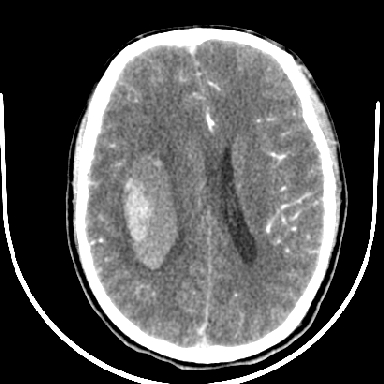

标题: CT6056:脑出血(血管畸形?) [打印本页]

标题: CT6056:脑出血(血管畸形?)

m 40突发头痛左侧偏瘫3小时

考虑高血压性脑出血,依据:

1是高血压性脑出血的好发部位,形态呈肾形,是高血压性脑出血的常见形状

2增强时占位效应加重了,考虑出血还没有停止

3病灶周围水肿不是太厉害,一般肿瘤出血水肿多非常明显

4病灶周围的‘软组织’影没有明显的强化

5至于脑血管畸形引起的出血,暂时没有看到明显的畸形血管影,也不太支持

支持右侧基底节脑出血

右侧基底节区脑出血.

支持右侧基底节区(主要为外囊区)原发性脑出血。

另附部分资料:“血液溢出血管外形成血肿,其内含有大量血红蛋白、血浆白蛋白,球蛋白,因这些蛋白对x线的吸收系数高于脑质,故ct呈现高密度阴影,ct值达40~90h,最初高密度灶呈非均匀一致性,中心密度更高,新鲜出血灶边缘不清。基底节区血肿多为“肾”型,内侧凹陷,外侧膨隆,因外侧裂阻力较小,故向外凸,其它部位血肿多呈尖圆形或不规则形”